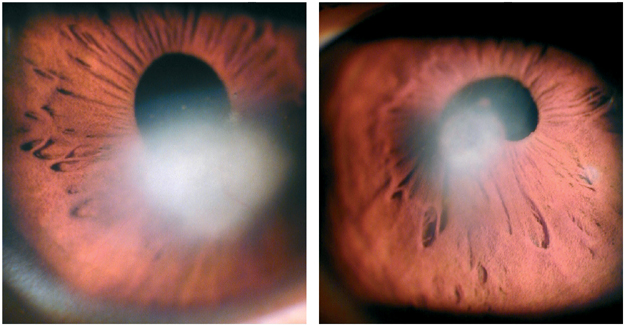

Is the evident cataract adequate to account for the symptoms, and the measurable reduction in contrast sensitivity and acuity. Double check the tear film, the corneal surfaces, the anterior and posterior chambers, and the retina to ensure you have not missed secondary pathology.